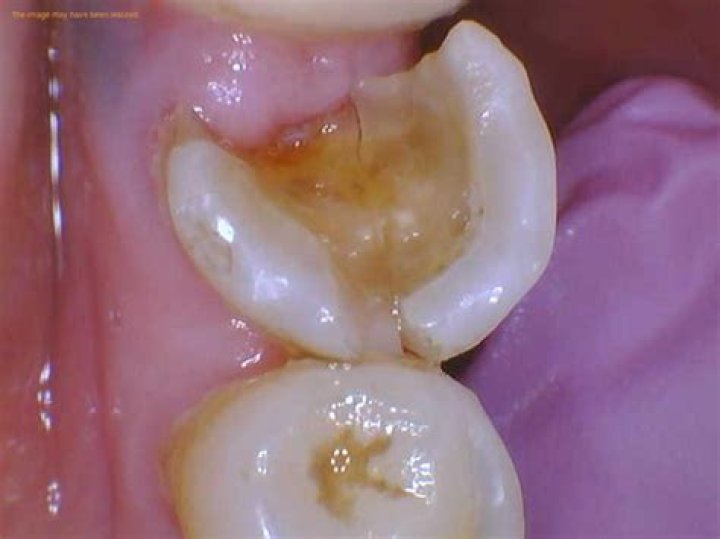

What does a rotten tooth look like?

If the process of tooth decay is allowed to continue, enamel will break down further. You may notice that a white spot on a tooth darkens to a brownish color. As enamel is weakened, small holes in your teeth called cavities, or dental caries, can form. Cavities will need to be filled by your dentist.

Why is my tooth turning black?

The tooth may also appear black when damage occurs from the inside. The most common causes of black teeth in these cases are decay or cavities. For example, a tooth with a pulp infection or a dead tooth may turn black. The damage starts on the inside and works its way to the surface.